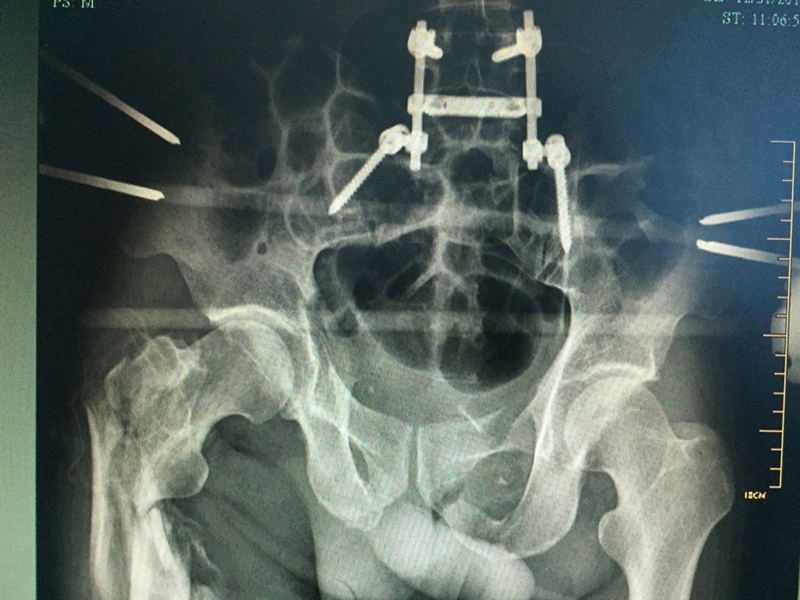

??? 當天,張成被轉入衢州市人民醫(yī)院救治。到達衢州市人民醫(yī)院之后,緊張的生命接力就開始了,傷情相當嚴重,張成生命垂危,重癥醫(yī)學科(ICU)醫(yī)護團隊立即投入戰(zhàn)斗,進行搶救;生命體征一轉平穩(wěn),待命的普外科、麻醉科、手術室醫(yī)護人員馬上進行脾臟切除術;最后把接力棒交給了骨科,方智敏主任會診后深知這是一個艱巨的任務,隨即帶領診療組探討治療方案,最終制定了詳細的診療計劃,前后對患者進行了三次大手術……從12月4日至12月31日,短短一個月的時間,張成就接受了五次手術。

??? 患者術后的部分X影像